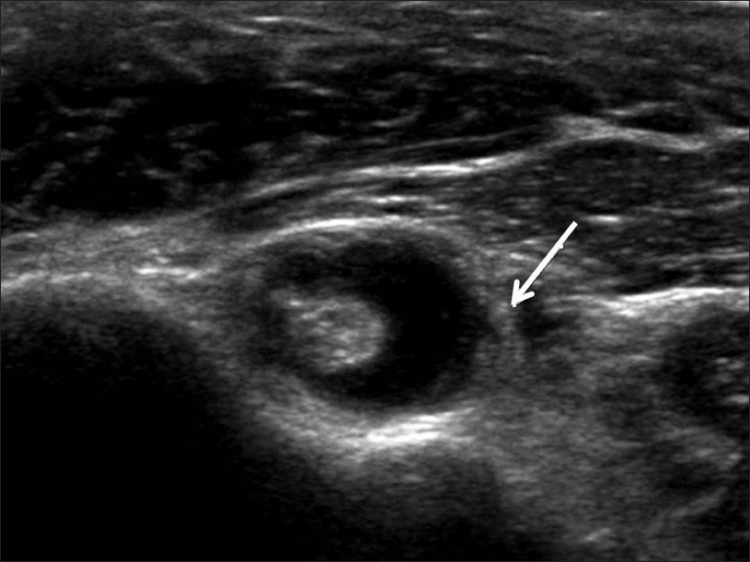

La ecografía del hombro comienza examinando el surco bicipital (BG) y la cabeza larga del tendón del bíceps braquial. El paciente está sentado frente al operador en una posición neutra, su mano colocada con la palma hacia arriba sobre el muslo. Se realiza una imagen de eje corto colocando el transductor sobre la metáfisis humeral proximal perpendicular al húmero. La imagen del eje largo del tendón se obtiene girando el transductor a una posición paralela a la diáfisis humeral [Figura 1]. Luego, se examina el tendón del subescapular. El brazo del paciente se fija sobre el flanco y el antebrazo se abduce en rotación externa. Se realizan vistas de eje largo y corto del tendón [Figura 2]. Los tendones infraespinoso y redondo menor se examinan desde una vista posterior del hombro. El paciente se gira 90°, su mano se coloca sobre el hombro opuesto y el transductor se orienta en el plano axial sobre la cabeza del húmero [Figura 3]. La articulación glenohumeral y la escotadura espinoglenoidea también se examinan en una vista posterior del hombro. El transductor ahora se mueve medial y caudalmente en el plano transversal hasta que se vea el margen posterior de la articulación glenohumeral y luego, más medialmente para mostrar la escotadura espinoglenoidea [Figura 4]. El tendón supraespinoso se escanea en una vista anterior del hombro. El paciente está sentado frente al operador. El brazo del paciente se coloca en una posición posterior, la mano dorsal en el ala ilíaca opuesta o la mano palmar en el ala ilíaca ipsilateral. Se obtienen vistas de eje largo y corto del tendón supraespinoso. Luego se realiza la exploración del manguito de los rotadores durante las maniobras dinámicas. El transductor se coloca sobre el acromion. El brazo del paciente se abduce con el codo flexionado a 90° o/y el brazo se extiende anteriormente [Figura 5]. Finalmente, se escanea la articulación acromioclavicular. La mano del paciente se coloca con la palma hacia arriba sobre el muslo. El transductor se coloca sobre la parte superior del hombro en un plano coronal [Figura 6].

Derrame de la articulación gleno-humeral [Figura 17], derrame de la bursa subacromial-subdeltoidea [Figura 18], bursitis calcificante [Figura 19], artropatías y dislocaciones de la articulación acromioclavicular [Figura 20], rotura del tendón del bíceps [Figura 21], sinovitis [Figura 22] y la luxación [Figura 23] son las principales patologías no relacionadas con el manguito rotador que se observan en la ecografía de hombro [Tabla 3]. [8-9] La ecografía es sensible para la detección de derrame de la articulación glenohumeral y derrame bursal subdeltoideo subacromial, incluso en pequeñas cantidades. La aspiración de líquido bajo guía ecográfica permite un diagnóstico preciso. La penetración intrabursal de depósitos calcificados en el tendón provoca una bursitis microcristalina aguda y dolorosa. La subluxación o dislocación de la articulación acromioclavicular aparece como un ensanchamiento de la cavidad articular y un abultamiento de la cápsula superior y el ligamento. La rotura de la cabeza larga del tendón del bíceps braquial suele generar un bulto en la parte anterior del brazo, conocido como "signo de Popeye". La rotura del tendón suele ocurrir a nivel intrarticular con retracción distal, dejando un surco vacío. En los desgarros agudos, el muñón del tendón aparece rodeado de líquido. La luxación del tendón del bíceps medial se diagnostica con ecografías transversales, que muestran el surco bicipital y el tendón que recubre la tuberosidad menor.#dieciséis#